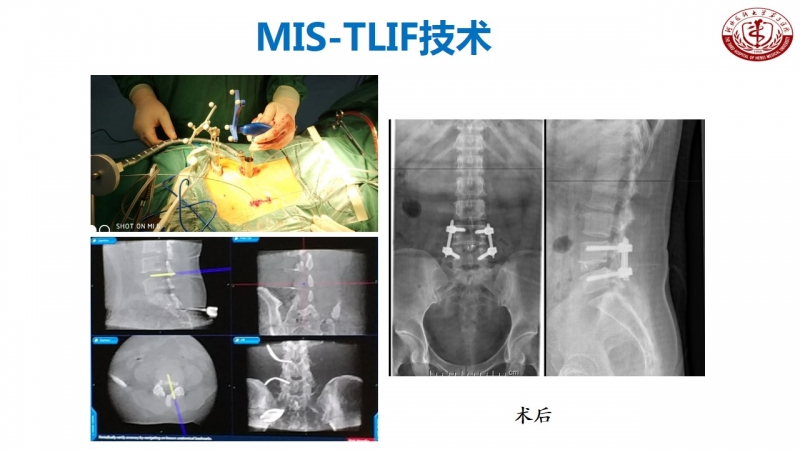

核心技术展示

科室发展,未来可期

作为脊柱外科的主任,丁文元教授时刻不忘科室的建设和发展。目前,河北医科大学第三医院脊柱外科共有33人,其中主任医师9人,副主任医师4人,主治医师11人,分三个病区,共120张床位,年门诊量66000余人次,年手术量4500余台,并开展了一系列脊柱高难手术,如复杂脊柱畸形截骨矫形术、复杂严重颈椎病前后路手术、胸腰椎前后路手术、上颈椎腰骶部复杂手术以及脊柱各种微创手术。

脊柱外科目前所开展的诊疗技术(滑动查看)

相信河北医科大学第三医院脊柱外科在新的学科带头人的领导下,不忘初心,砥砺前行,做好脊柱基础及临床研究,逐步提高学术影响力,攻克临床上各个难关,提升临床诊疗水平,使脊柱外科朝着精准化、微创化、显微化、智能化发展,造福更多患者。